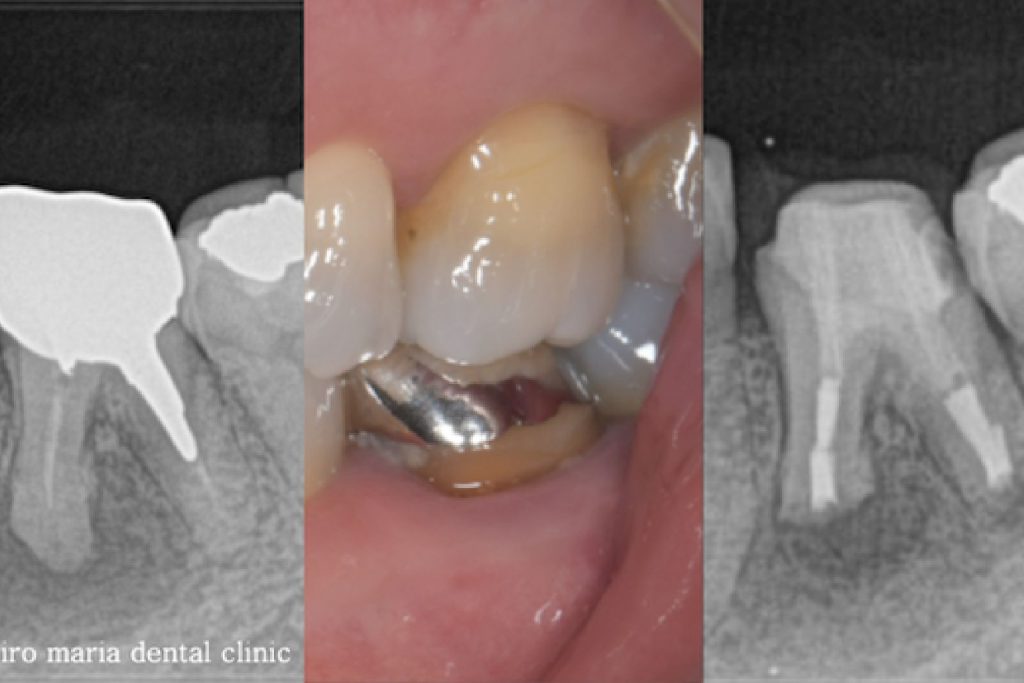

今回の症例は10年以上の間フィステル(瘻孔)がある状態で放置したケースです。患者様はそもそも歯科治療に恐怖心があり、歯ぐきにできたフィステルが悪いものと診断されることが怖く、歯科治療から遠ざかっておられました。

最近になって痛みを伴う腫れが頻繁に発症するようになったことに耐え難くなり、当院を受診されました。

当院を受診する前にも根管治療を行なっている歯科医院を受診するも、抜歯しインプラントを勧められたとのことでした。当院の診査では抜歯をするほどの所見は確認できず、通常通りの精密根管治療を行うことをご提案させていただきました。

当院にて根管治療を開始するも根管治療の反応は乏しく、術前に確認できていた症状の改善は認められませんでした。その為、この患者様には歯根端切除術を追加で行い、マネージメントをさせていただくこととなりました。

歯根端切除術時に根尖を3mmほど切断したところ、根尖を取り囲むほどの歯石が確認され、この歯石の感染が根尖性歯周炎の治癒を妨げていた可能性がありました(写真)。